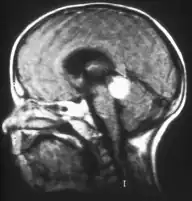

Traditional ultrasound B scan can detect calcifications in the tumour while high-frequency ultrasound B scan is able to provide higher resolution than the traditional ultrasound and determine the proximity of the tumour with front portion of the eye. MRI scan can detect high-risk features such as optic nerve invasion; choroidal invasion, scleral invasion, and intracranial invasion. CT scan is generally avoided because radiation can stimulate the formation of more eye tumours in those with RB1 genetic mutation.[24]

Aspect of trilateral retinoblastoma on MRI -